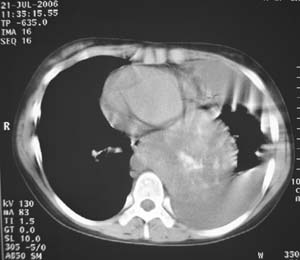

女性,17岁,一年前因股骨病变截肢,现胸憋。

左肺巨大肿块,内散在斑点状高密度骨化影,右肺见多发结节灶,双侧胸膜局限性增厚。有骨肉瘤病史,支持骨肉瘤手术后转移。